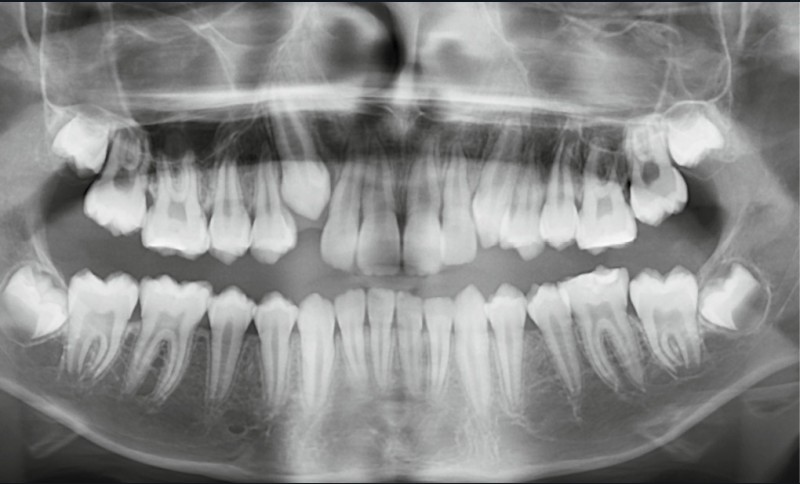

L’examen clinique montre une MIH sévère sur 16, 26, 36 et 46, et modérée sur 11 et 21.

Le moment de l’extraction est essentiel : à cet âge, les deuxièmes molaires n’ont pas terminé leur édification radiculaire, ce qui favorise leur mésialisation [2]. Néanmoins, la direction d’éruption, surtout mandibulaire, reste difficile à prévoir, et la présence des troisièmes molaires ne garantit pas leur éruption correcte [3].

Le choix d’extraction dépend de l’âge, du stade de développement des secondes molaires, de la présence des troisièmes molaires, de la DDA et des relations squelettiques.